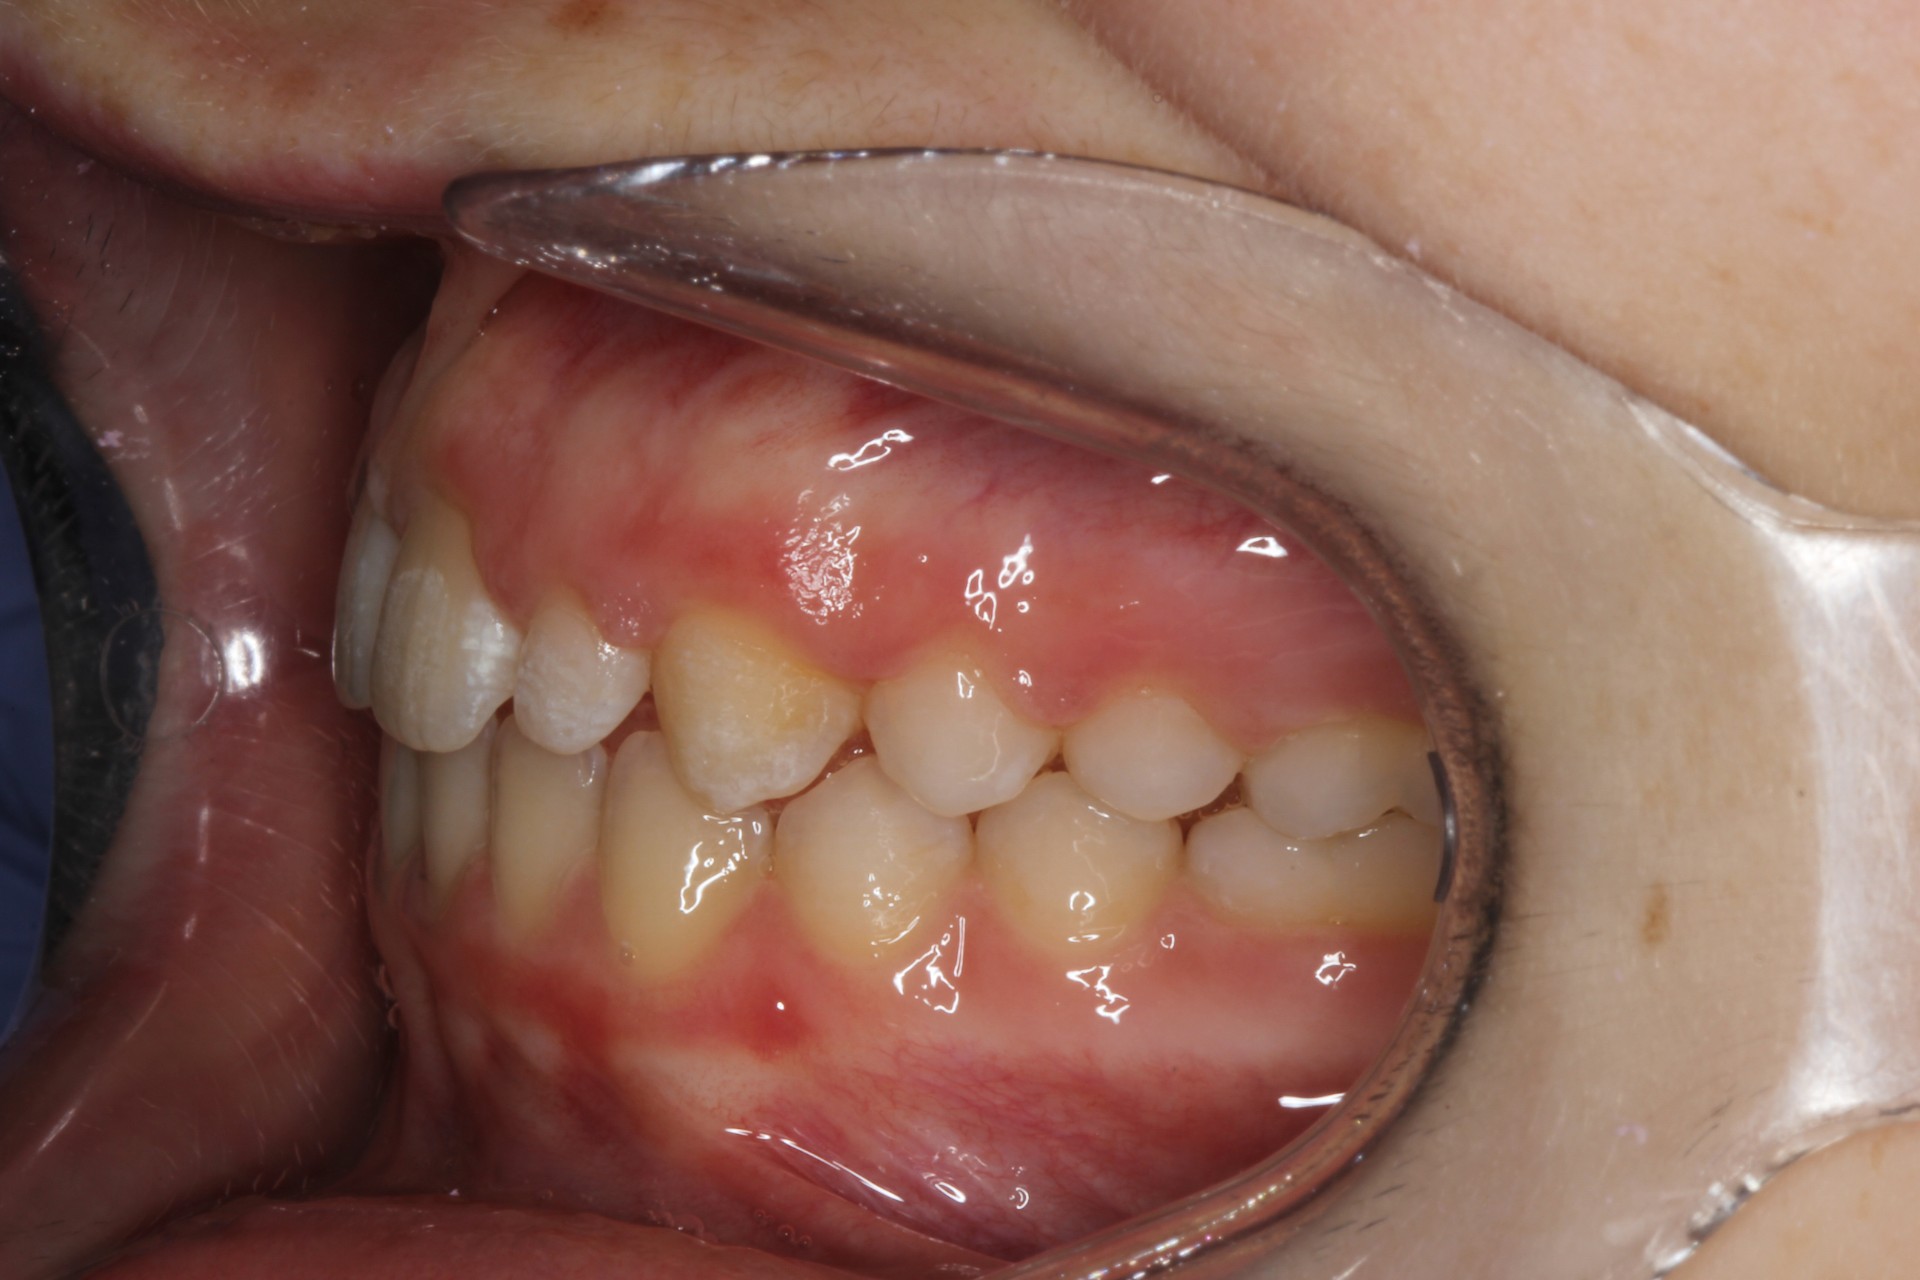

Protruding front teeth – Child case